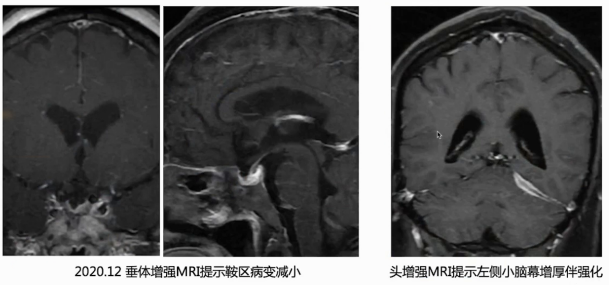

近2年前出现头痛,1年前出现多尿、多饮。外院垂体MRI提示鞍区占位,去氨加压素可控制尿量。病程中曾多次接受激素冲击治疗,治疗后鞍区病变缩小、症状缓解,但激素减量期间头痛反复,鞍区病变再次增大。

初始治疗采用足量激素加免疫抑制剂,激素逐渐减量。在三年随访过程中,激素量由50 mg qd逐渐减量至2.5 mg qd,免疫抑制剂也进行了调整。期间患者垂体病变相对稳定甚至有所减小,硬脑膜病变稳定,纵隔占位经心脏MRI随访大小无明显增长。